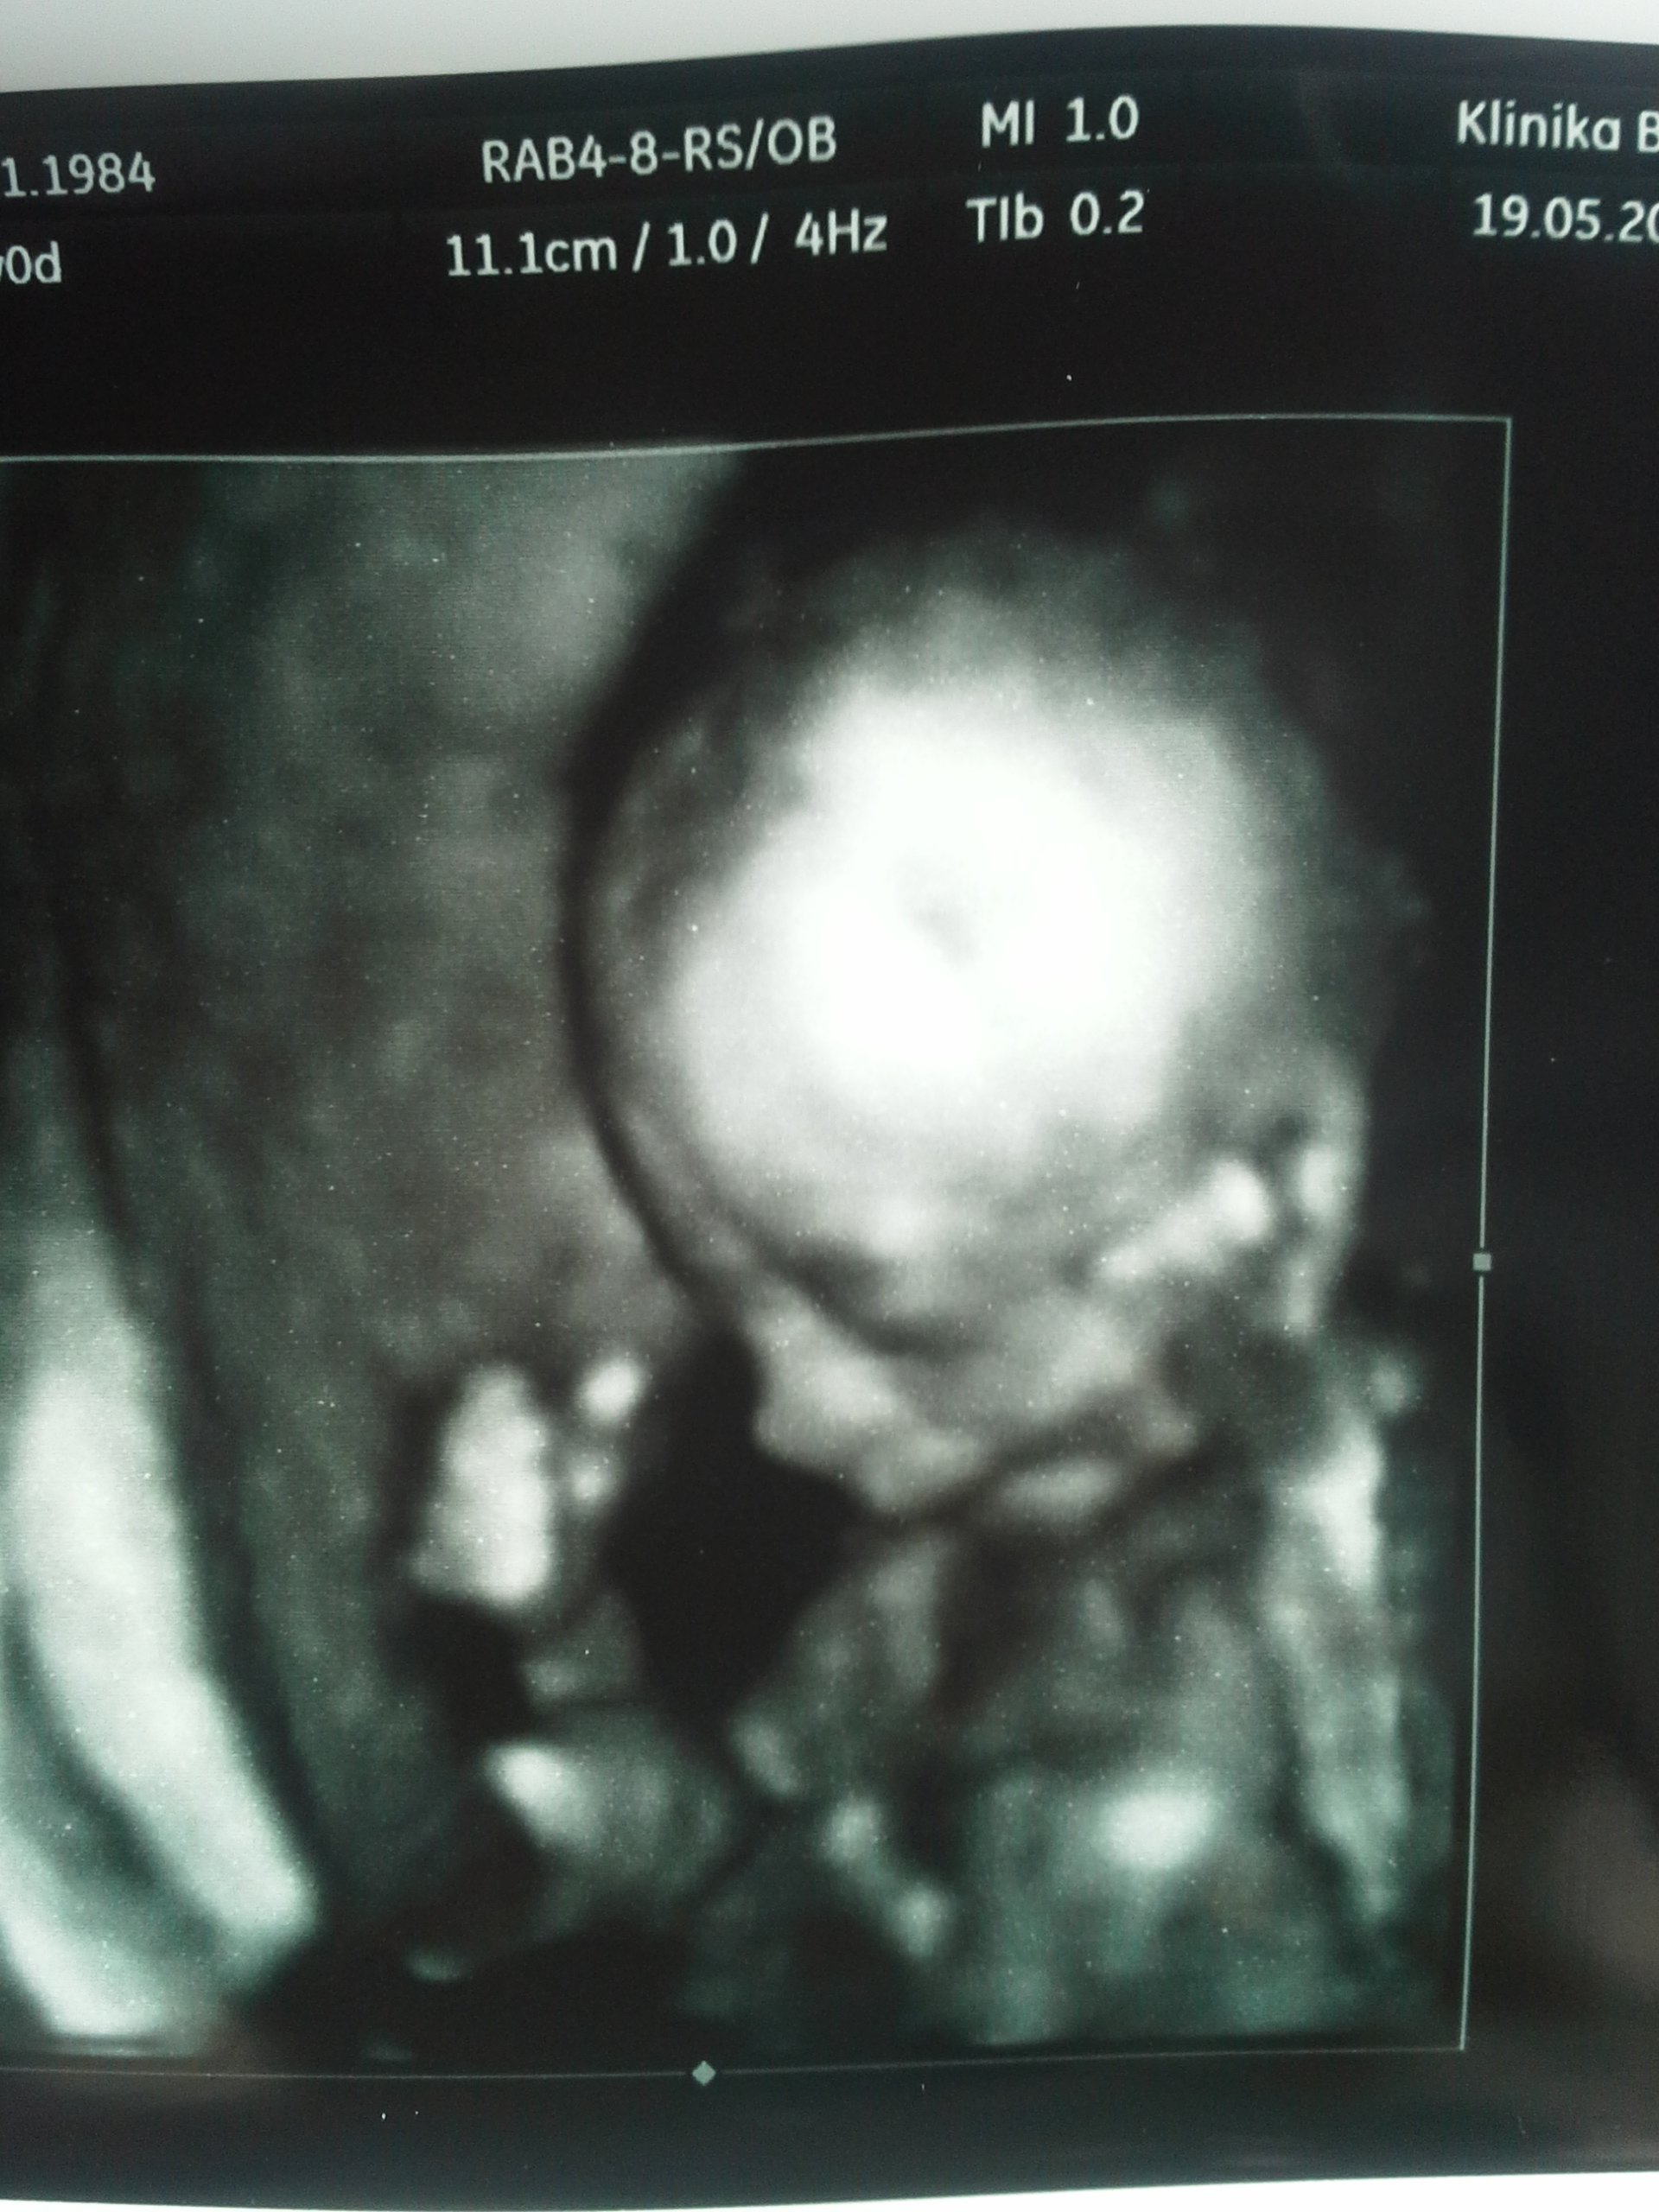

Wczoraj robione [emoji23] [emoji23]